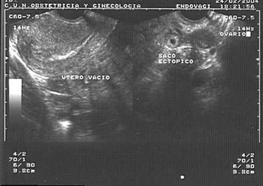

Certeza: La ecografía transvaginal es la prueba confirmatoria de embarazo. A las 4.5 semanas, se observa saco gestacional; a las 5 semanas, se encuentra embrión, y a las 6 semanas es posible auscultar los latidos cardiacos fetales con el doppler . También se considera la percepción de movimientos fetales por parte del médico.

Figura 11. Ecografía de I trimestre Examen de certeza para confirmar un embarazo eutópico y viable